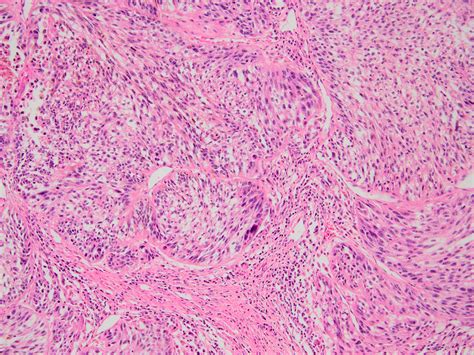

Receiving a medical diagnosis involving the term Spindle Cell Neoplasm can be an overwhelming experience, often filled with uncertainty and concern. To navigate this diagnosis effectively, it is essential to understand what these cells are, how they behave, and why this term is used as a broad descriptor rather than a final, specific diagnosis. At its core, this term refers to a group of tumors characterized by the presence of elongated, spindle-shaped cells when viewed under a microscope. Because many different types of tissue can produce these specific cell shapes, the diagnosis is essentially a starting point for pathologists to determine the exact nature and origin of the growth.

In pathology, the term Spindle Cell Neoplasm is a descriptive classification. It tells a medical team that a biopsy has revealed cells that are longer than they are wide—resembling the shape of a sewing spindle—but it does not immediately clarify whether the tumor is benign (non-cancerous) or malignant (cancerous).

These cells are structural components of the body’s connective tissues, including muscle, fat, fibrous tissue, and nerves. When these cells begin to grow uncontrollably, they form a mass that pathologists identify as having "spindle cell morphology." Because this morphological trait is shared by a vast array of conditions, pathologists must perform secondary testing, such as immunohistochemistry, to identify specific proteins or markers present on the cells.

The diagnostic journey for a Spindle Cell Neoplasm involves a multidisciplinary approach. Once a pathologist identifies the spindle-shaped cells, they initiate a process to narrow down the diagnosis. This is critical because the treatment plan for a benign fibroma is vastly different from that of a high-grade sarcoma.